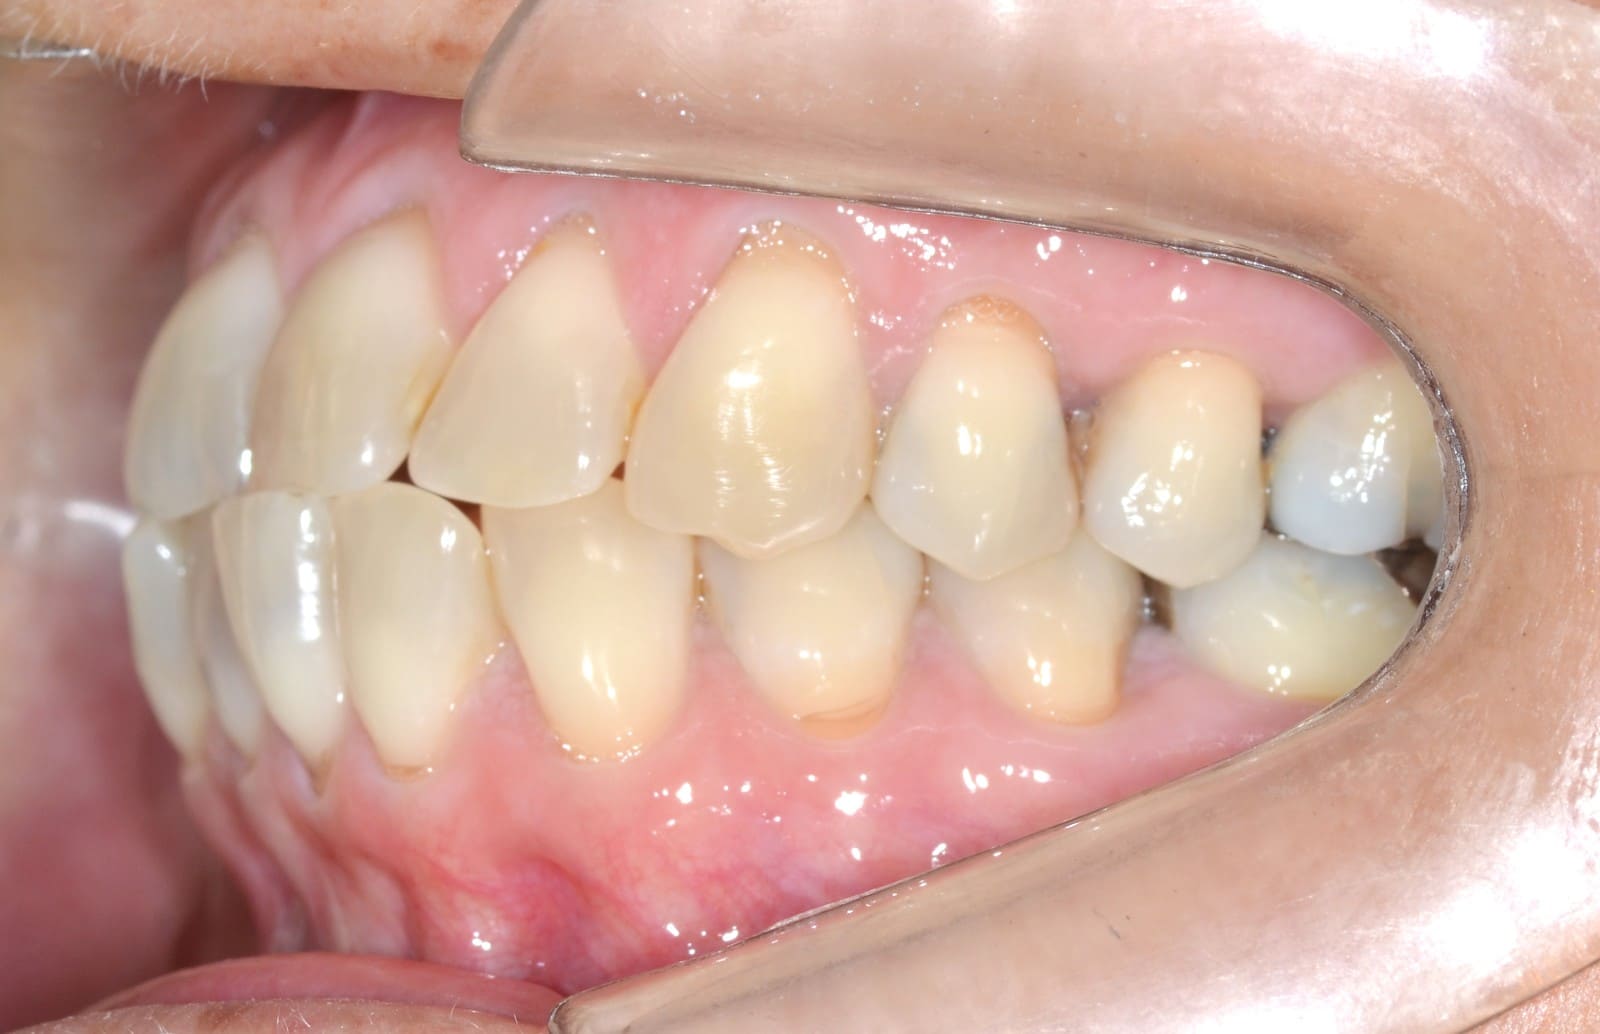

Initial

Final

- Anterior crossbite

- Class III

- Crowding

- Mandibular midline deviation

- Rotations